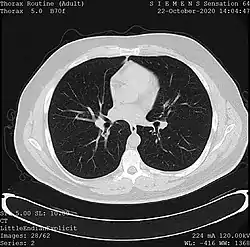

![]() One frame of a CT scan of the chest showing the heart and lungs | |